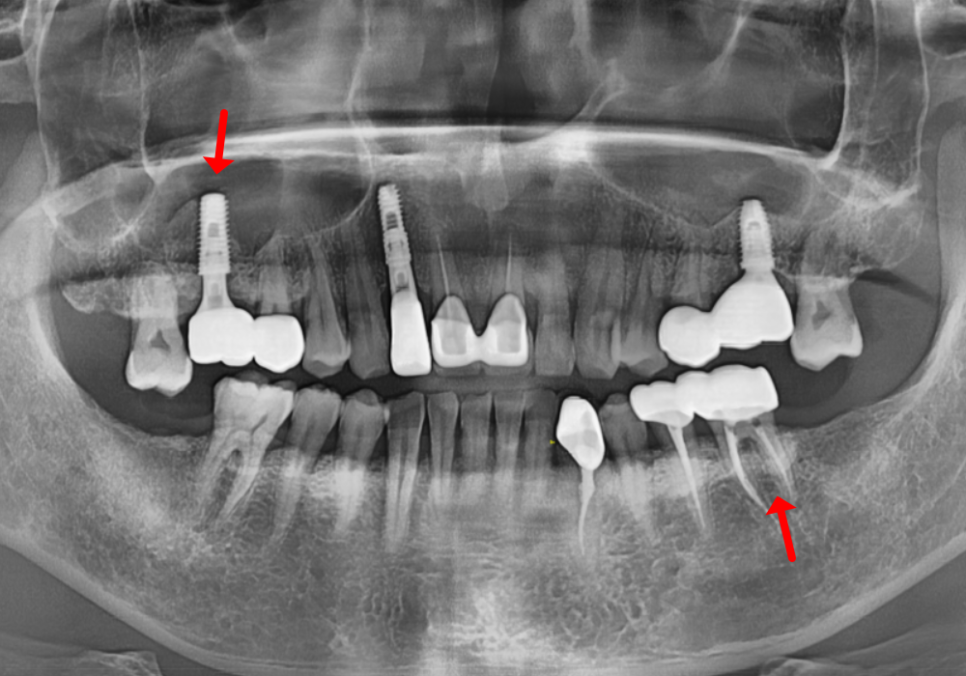

첫 번째 사례, 구멍 난 금니를 가지고 오신 환자분

상일역 치과, 오래된 금니 빠짐

처음 환자분이 오셨을 때는

오른쪽 위 어금니 금니가

빠져서 내원하셨는데요,

240812

가져오신 금니를 받아들고 살펴보니

세월의 흔적이 역력하더군요.

오랜 시간 씹는 힘을 견디느라

금니 표면이 닳아서,

구멍이 '뻥' 뚫려 있는 상태였습니다.

240812 상일역 치과, 오래된 금니 빠짐

입안을 들여다보니

상황은 생각보다 심각했습니다.

금니에 생긴 그 작은 구멍 틈새로

음식물 찌꺼기가 야금야금 들어가면서,

보철물 안쪽의 치아가

아주 심하게 삭아버린 상태였죠.

충치를 제거하자마자

남은 치아 머리 부분이

마치 모래성처럼 힘없이

부서져 버리고 말았습니다.

설상가상으로 뿌리 끝에는

거뭇한 염증 주머니까지 잡혀 있었죠.

염증으로 녹아내린 잇몸뼈를

단단하게 보강하는

뼈이식을 하고,

임플란트를 식립했습니다.

240831

그리고 뼈와 임플란트가

한 몸처럼 단단히 굳을 때까지

5개월을 묵묵히 기다린 뒤에야,

튼튼한 새 치아를 만들어 드릴 수 있었습니다.

상일역 치과, 오래된 금니 빠짐 241207